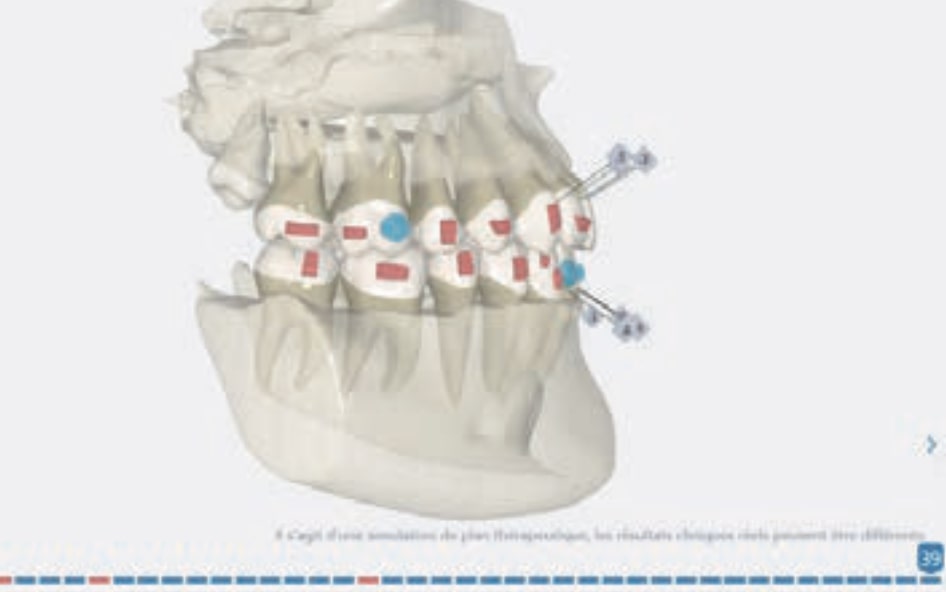

- Distalization of the Third and Fourth Quadrants: Move the teeth distally in these quadrants to achieve a Class I relationship using the A8 protocol, improving the patient’s dental alignment and occlusion.

Treatment setup